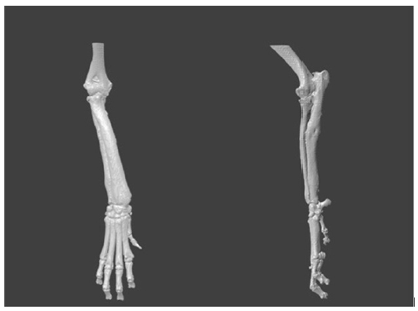

Radiography of both forelimbs (radius and ulna including the proximal and distal joint) revealed right forelimb angular deviation because of a possible premature physeal closure of the distal ulnar growth plate (Figure 1A).

Figure 1A: Surgical planning: cranio-caudal and medio-lateral radiographs of right antebrachium at the preoperative moment.

Surgical correction was prescribed; the preoperative planning consisted of developing a customized device to aid the surgeon during surgery. A CT study of both forelimbs was carried out, including the elbow and carpal joints. The dog was placed in sternal recumbency with the forelimbs extended cranially, allowing the carpi and metacarpi toremain in a neutral position. A CT scan was performed in a 2-slice CT scanner witha 1mm gap between cuts, starting in the proximal humerus, and extending to include the metacarpi. The CT findings wereexported to DICOM format, allowing further manipulation, resulting in a 3D reconstruction of the pathological limb (Figure 1B).

The method used to plan the surgery is described by Domenech et al. [10]. This methodallows for correction of angular deformity in a long bone by means ofclosed wedge ostectomies. Thismethod aims to minimize loss of bone length. This methodology only requires the availability of 3-D reconstruction of the diseased bone and the correct definition of the proximal and distal joint planes (Figure 1C). In this case, the 3-D model was obtained by reconstruction information obtained by CT, which was then examined by a surgeon. A surgical plan was formed based on the bone’s anatomical points, which was determined the joint planes.

Figure 1C: In vitro 3D reconstruction of the diseased bone and the correct definition of the proximal and distal joint planes.